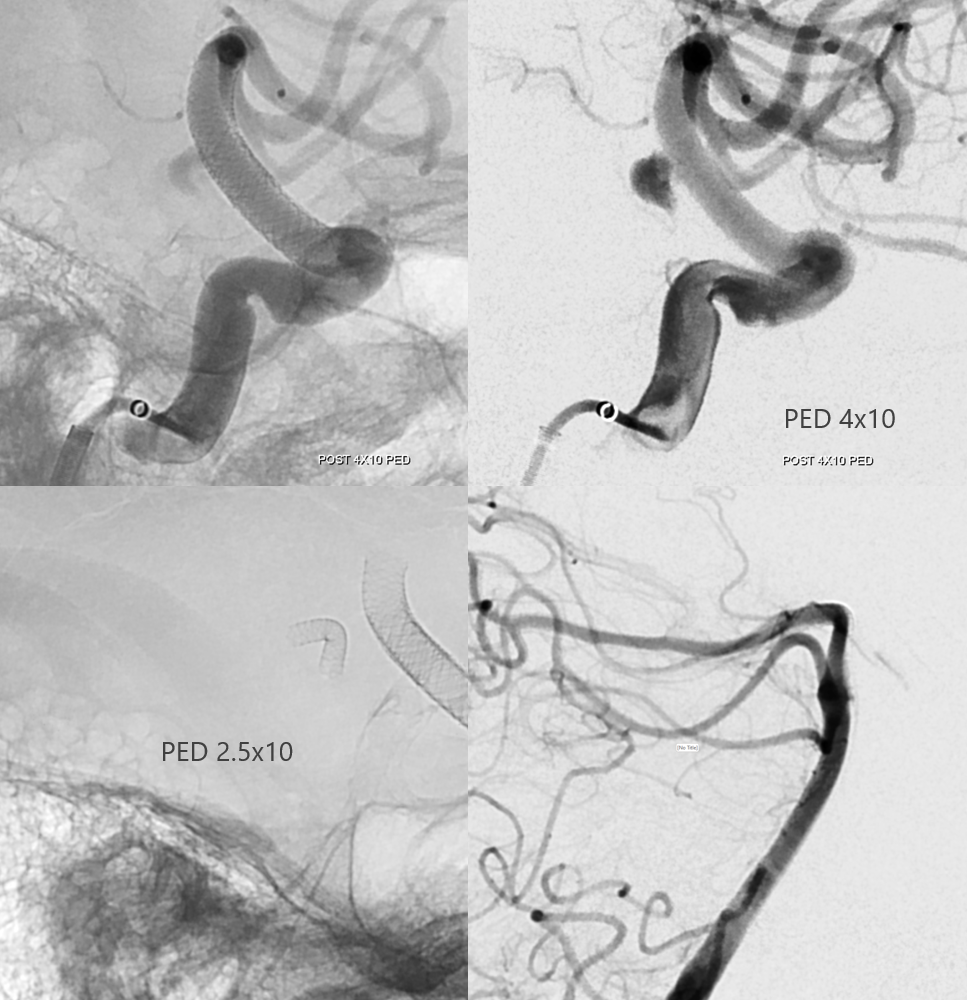

What to do? Coiling it through P1 risks the thalamoperforator. Undercoiling is not a good idea. The solution is to Pipe across the P1

This is changing flow dynamics for sure. One year later, finally gone. Note how the aneurysm deflated, closing the distance between the two pipe constructs.

Conclusion — real flow modifications are necessary to address this problem.